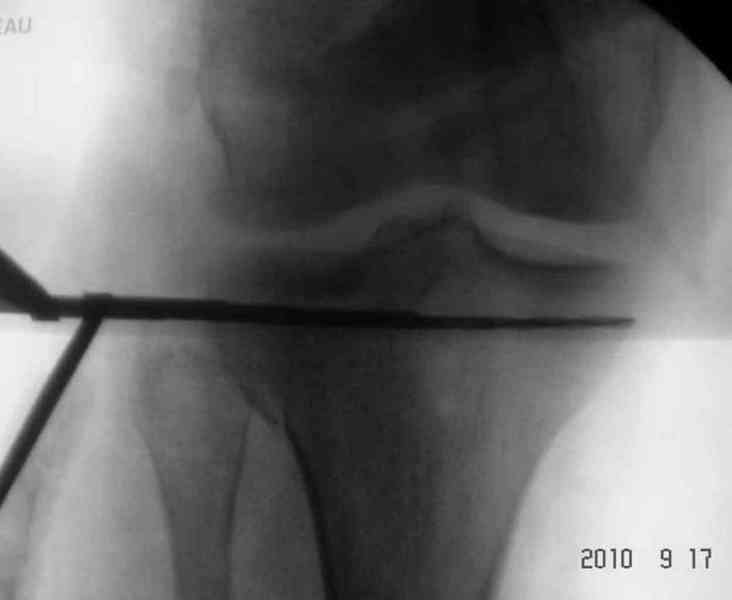

Снимки до и после закрытой репозиции

На представленном после операционном снимке нет репозиции, на что указывает низкое положение тибиального плато и перекрытие кортикальных пластинок в метафизарной части - указано стрелкой. Обычно чрескожную фиксацию я применяю

Мыщелок левой б/б кости репонирован закрыто, на контрольной рентгенограмме репозиция удовлетворительная, фиксировано спицами. гипсовая повязка.

Репозиция внутрисуставных переломов неудовлетворительная и не адекватна.

сценарий и для перелома наружного мыщелка б.б.- передний фрагмент стоит на месте, а задний не репонирован - в таком положении оставлять фрагменты нельзя, суставная поверхность должна быть реконструирована.

В лечении переломов пилона восстановление длины малоберцовой является индикатором и ориентиром для успешного лечения. Первый этап восстановления по длине не удался, малоберцовая остается короткой, и репозиция суставной поверхности осталась неудовлетворительной. Длина передней колонны не восстановлена, а в дистальном фрагменте имеется флексия. Оставлена без внимания потеря кости в метафизе. Шурупы 4.5 мм будут выступать после спадения отека, и возможно будут причиной мягкотканого осложнения в гипсе.